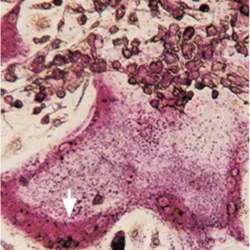

Lipids and Calcification

We have introduced the Lipid Hypothesis of osteoporosis, showing that bioactive phospholipids that trigger cardiovascular calcification also promote osteoporosis, inhibiting differentiation of bone forming osteobalsts while promoting differentiation of bone resorbing osteoclasts. Light microscopy of bone-marrow derived a multinucleated (arrow) osteoclast stained for tartrate-resistant acid phosphatase (TRAP).